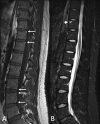

Imaging is an integral part of the management of patients with ankylosing spondylitis and axial spondyloarthritis. Characteristic radiographic and/or magnetic resonance imaging (MRI) findings are key in the diagnosis. Radiography and MRI are also useful in monitoring the disease. Radiography is the conventional, albeit quite insensitive, gold standard method for assessment of structural damage in spine and sacroiliac joints, whereas MRI has gained a decisive role in monitoring disease activity in clinical trials and practice. MRI may also, if ongoing research demonstrates a sufficient reliability and sensitivity to change, become a new standard method for assessment of structural damage. Ultrasonography allows visualization of peripheral arthritis and enthesitis, but has no role in the assessment of axial manifestations. Computed tomography is a sensitive method for assessment of structural changes in the spine and sacroiliac joints, but its clinical utility is limited due to its use of ionizing radiation and lack of ability to assess the soft tissues. It is exciting that with continued dedicated research and the rapid technical development it is likely that even larger improvements in the use of imaging may occur in the decade to come, for the benefit of our patients.